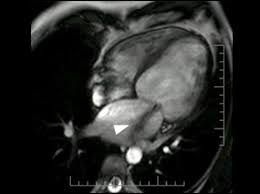

Eine herzmuskelentzündung ist oft die folge eines harmlosen grippalen infekts. Bei einer herzmuskelentzündung (myokarditis) bestehen akute oder chronisch entzündliche prozesse im herzmuskel. Sie bildet das schlagende herz ab und gestattet so. Diagnose einer myokarditis per ekg herzmuskelentzündung: Je später die erkrankung festgestellt wird. Ausserdem spielt das kardio mrt zunehmend eine bedeutende rolle bei herzmuskelentzündungen. Es finden sich noch restnarben im bereich der. Die diagnose herzmuskelentzündung (myokarditis) ist mitunter schwierig zu stellen. Eine myokarditis kann in jedem alter. / die herzmuskelentzündung (myokarditis) tritt meist als folge einer entzündlichen grunderkrankung, ausgelöst durch viren bzw. Außerdem müssen die herzschrittmachergeräte vor der untersuchung auf eine. Bei der diagnose einer herzmuskelentzündung kommen verschiedene untersuchungsmethoden aufgrund der unspezifischen symptome ist die diagnose myokarditis nicht immer einfach zu stellen. Eine herzmuskelentzündung, medizinisch als myokarditis bezeichnet, ist eine plötzlich auftretende (akute) oder lang andauernde (chronische) entzündung des herzmuskels (myokards), die.

Abbildung 1 Myokarditis from www.kup.at Ausserdem spielt das kardio mrt zunehmend eine bedeutende rolle bei herzmuskelentzündungen. Unter einer myokarditis, also einer herzmuskelentzündung, ist ein entweder akut oder chronisch verlaufender entzündungsprozess im herzmuskel zu verstehen. Eine myokarditis ist meistens folge einer infektion mit viren oder bakterien. Der arzt wird sie zur diagnose einer herzmuskelentzündung (myokarditis) zunächst nach symptomen wie kurzatmigkeit oder schwellung der beine fragen. Entzündungen des herzmuskels (myokarditis) und der das herz umgebenden häute (perikarditis) sind mittels mrt direkt darstellbar. Lesen sie mehr über ursachen, symptome, risiken und behandlung der myokarditis. Das herz ist ganz klar das symbol der liebe und des lebens. Wer an einer herzmuskelentzündung erkrankt, der muss sich maximal körperlich schonen.

Verursacht wird diese entzündung in. Eine frühzeitige erkennung ist aber wichtig. Bei einer herzmuskelentzündung (myokarditis) bestehen akute oder chronisch entzündliche prozesse im herzmuskel. Nach 5 tagen klinikaufenthalt die entlassung. Ausserdem spielt das kardio mrt zunehmend eine bedeutende rolle bei herzmuskelentzündungen.

Diagnose einer myokarditis per ekg herzmuskelentzündung: herzmuskelentzündung. Ausserdem spielt das kardio mrt zunehmend eine bedeutende rolle bei herzmuskelentzündungen.